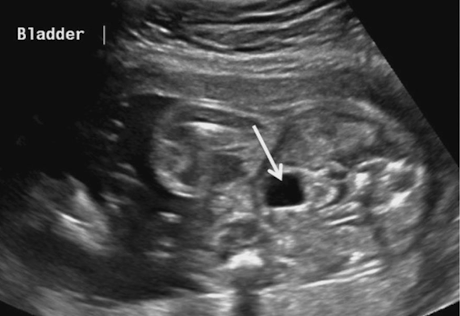

bladder

distended bladder should be seen by 13wks

empties and fills at least once every 30 minutes

if not identified on exam; exam must be repeated within 24 hours

empty bladder is an indication of abnormality

SONO:

anechoic (fluid-filled)

document in LONG and TRV